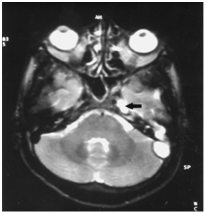

Although a CT scan is not required for patients with facial palsy, it can be useful in therapeutic planning. When cholesteatoma involves the Fallopian canal, it may also erode structures such as the labyrinth or tegmen. When petrous apicitis is suspected, a CT scan should be performed to make the diagnosis and to evaluate surrounding anatomy. CT scan will also aid in the diagnosis of intracranial complications that often accompany this condition.MRI accurately shows the site and extent of the apical abscess (Figure 4).

Figure 4 Axial T2 weighted MRI showing hyper intense region (arrow) in the left petrous apex.